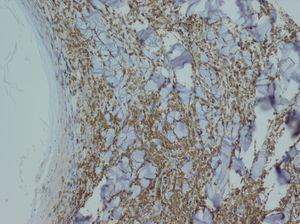

Realizamos una biopsia de una de las lesiones foliculares del abdomen (fig. 3), en cuyo estudio histopatológico apreciamos un infiltrado en banda epidérmico y un denso infiltrado dispuesto alrededor del infundíbulo piloso con afectación de la interfase en dermis. Con técnicas de inmunohistoquímica observamos que dicho infiltrado está compuesto por células linfoides de pequeño a mediano tamaño que exhiben núcleos irregulares e hipercromáticos y expresan el marcador CD3 (fig. 4).

Fig. 4.--Tinción inmunohistoquímica para el marcador CD3. (Hematoxilina-eosina, x40.)